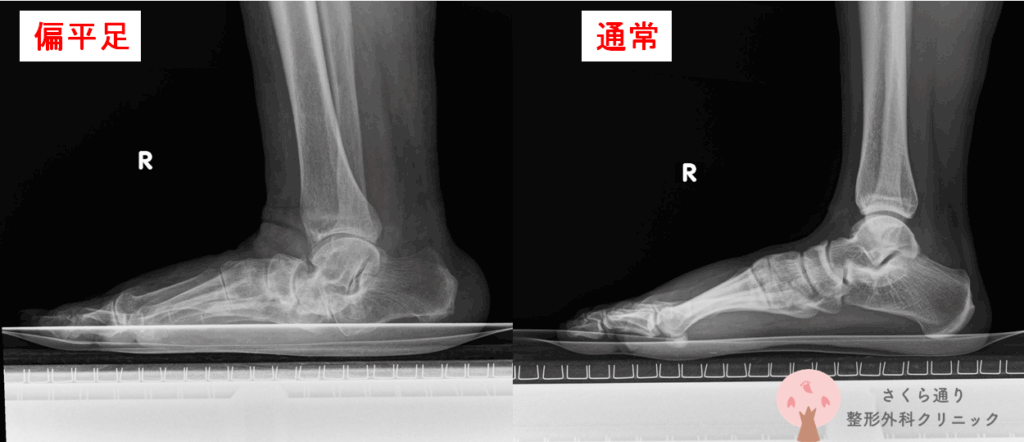

前回の「段差カーフレイズ編」では、“足首を支える土台=ふくらはぎの筋力”を鍛える方法をご紹介しました。今回の第2回では、足首を守るうえで欠かせないもう1つの要素、つまり「足裏のアーチ」を鍛えるトレーニングについて詳しくお伝えします。

足裏のアーチは、ただの形ではありません。衝撃を吸収し、身体のバランスを整え、足首や膝にかかる負担を軽くしてくれる重要なクッション機能を担っています。

このアーチが弱ると、足首がグラつきやすくなり、捻挫が癖になりやすくなる——という負のループに陥ってしまいます。

特に「足裏アーチ」が弱くなると、以下のような症状が出やすくなります。

タオルギャザーは、このアーチ構造の“柱”を鍛えるため、捻挫予防だけでなく、外反母趾の予防、扁平足対策、着地衝撃の吸収力アップにも役立ちます。